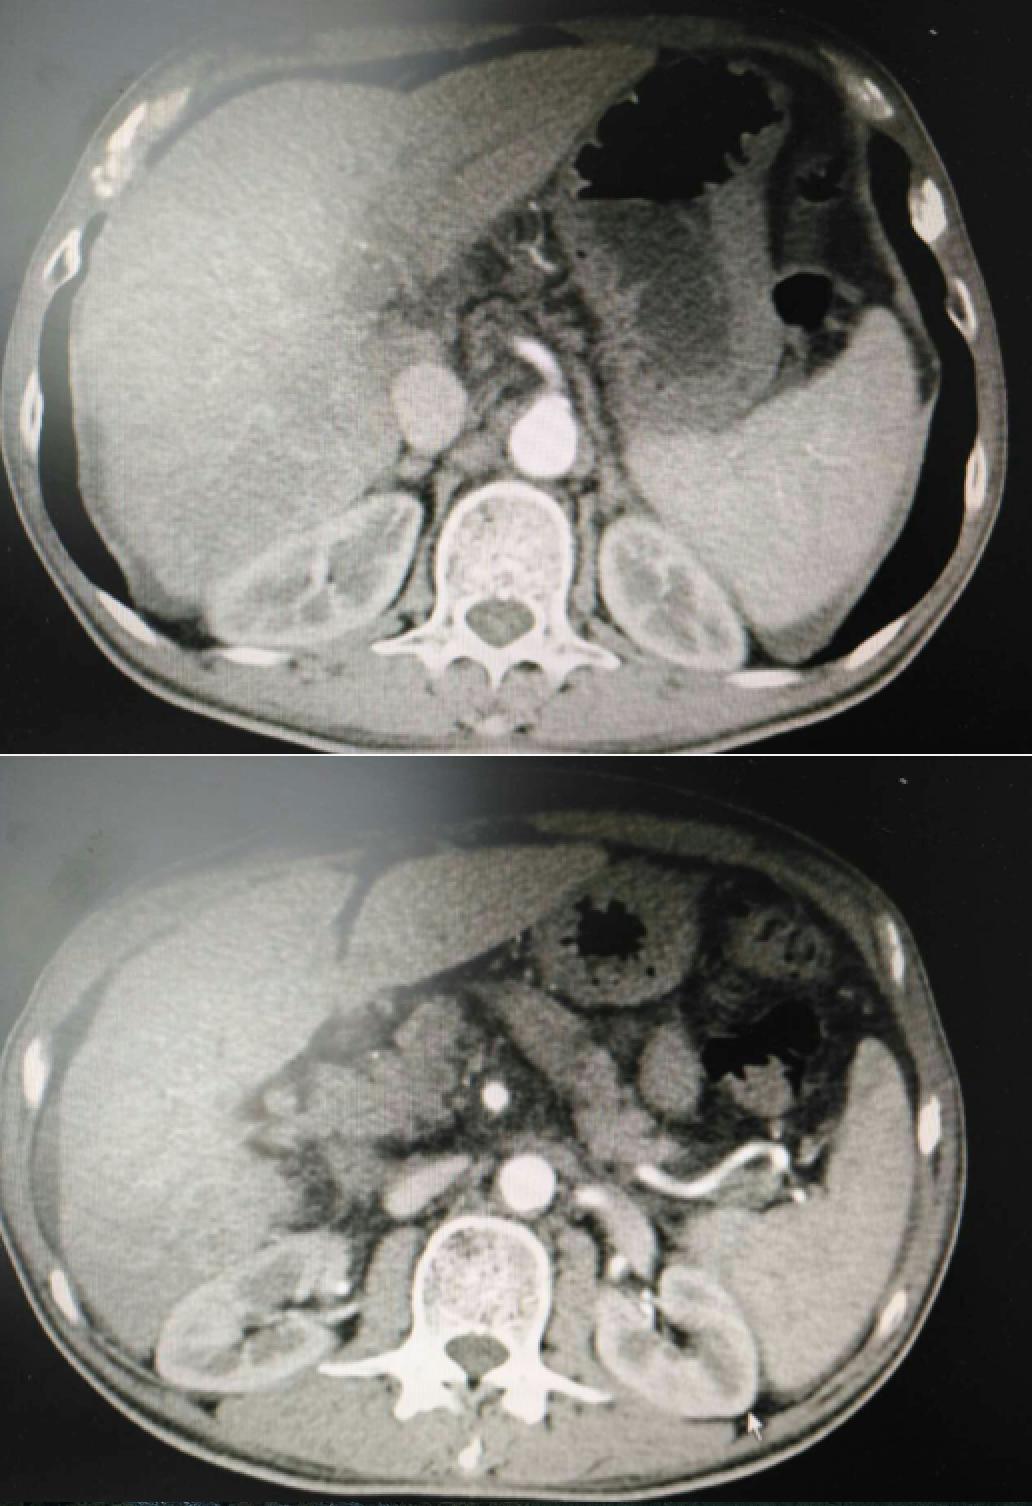

患者因纳差、烧心、腹痛、腹胀2月,于2016-01-17在某县人民医院行腹部CT示肝癌并门脉癌栓形成。分别于2016-01-22、2016-02-19于某市医院行两次TACE术(具体不详)。患者介入术后规律服用抗乙肝病毒、保肝、提高免疫力等药物治疗。2016-02-03至2016-04-30在某省立医院行5周期CIK免疫治疗。2016-05-18至2016-05-25于我院行射波刀治疗门静脉癌栓,具体放疗计划为:42Gy/7F。2016-06-24在我院行肝右动脉化疗栓塞术+肝右动脉灌注化疗术+间接门脉灌注化疗术,术中化疗总量,吡柔比星2mg、顺铂12mg、氟尿嘧啶250mg。分别于2016-05-10、2016-05-27、2016-06-13、2016-07-01、2016-07-27、2016-08-22、2016-09-19、2016-10-07、2016-10-19、2016-11-18、2016-12-18、2017-02-18行12周期免疫治疗。自2016-05-12起患者间断口服靶向药物阿帕替尼250-500mg/d,血压维持在220-130/95-70mmHg,血压升高期间伴上腹部不适,左侧为著,并向腰背部放射,偶尔反酸、烧心,剑突下疼痛,口服抑酸剂或进食后缓解,临床诊断为十二指肠溃疡,目前口服奥美拉唑、马来酸依那普利、氢氯噻嗪等药物对症降压。2017-03-02于我院行第二次肝右动脉化疗栓塞术+肝右动脉灌注化疗术+间接门脉造影术+肠系膜上动脉灌注化疗术。术中化疗总量,洛铂10mg、氟尿嘧啶500mg、吉西他滨400mg。目前间或皮下注射胸腺法新、重组人干扰素α-2b提高免疫力及慢性乙型病毒性肝炎治疗效果。

患者相关影像资料